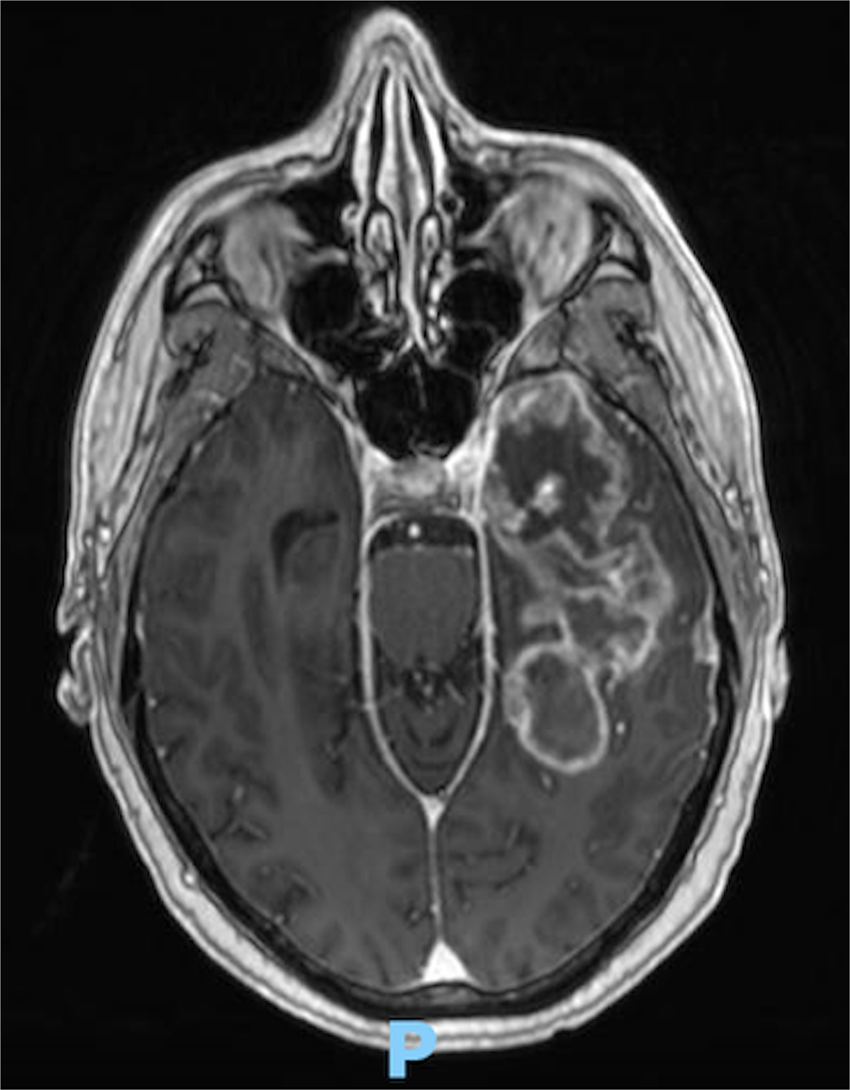

T1-weighted gadolinium-enhanced axial MRI brain demonstrating a high complexity lesion with a 5.7% likelihood of complete resection.